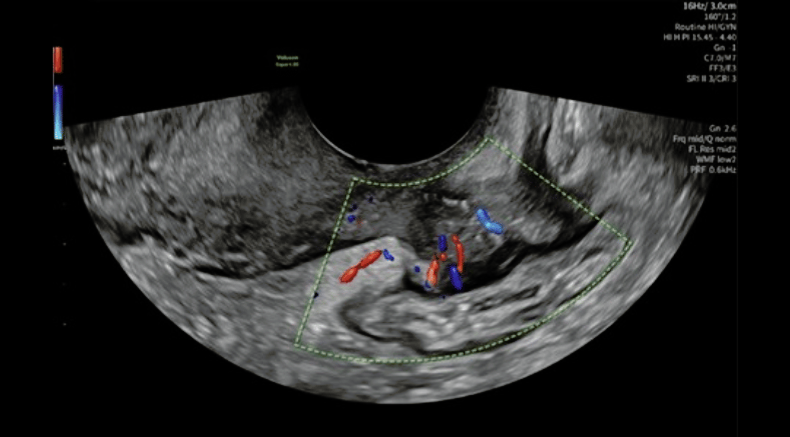

2D transvaginal color Doppler ultrasound imaging in longitudinal view showing marked vascularity of the endometriotic nodule, consistent with pregnancy-related decidualization

Barra, F., Maramai, M., Olcese, F., Beleva, D., Gustavino, C. and Ferrero, S. (2026), Decidualized posterior compartment deep endometriosis: three-dimensional rendering and Doppler-based vascular assessment. Ultrasound Obstet Gynecol. https://doi.org/10.1002/uog.70225